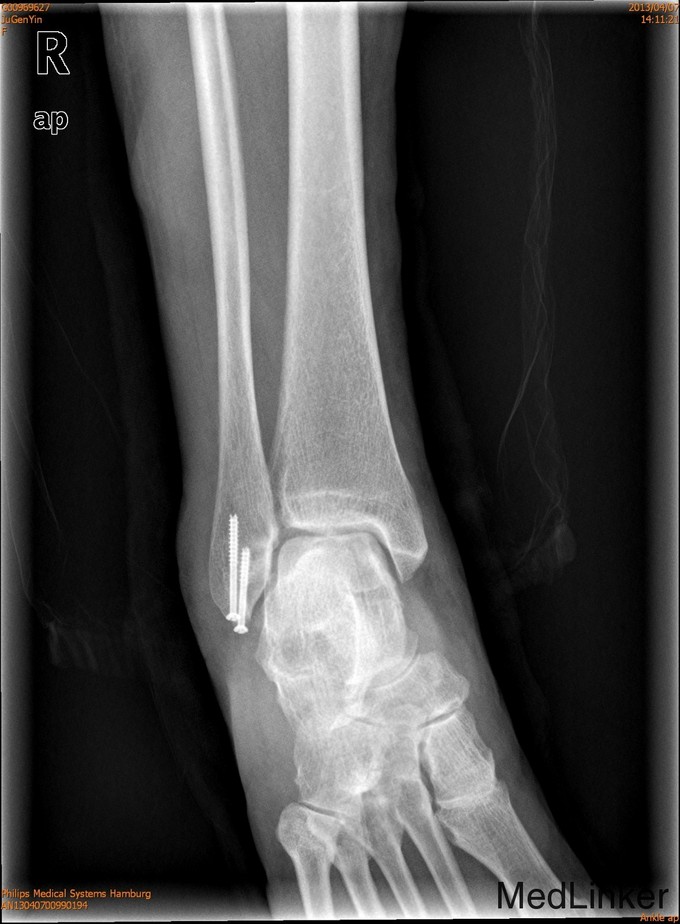

2年后随访患者活动可,内固定位置可,螺钉未予取出。外踝骨折可导致踝关节不稳定,手术治疗效果可。